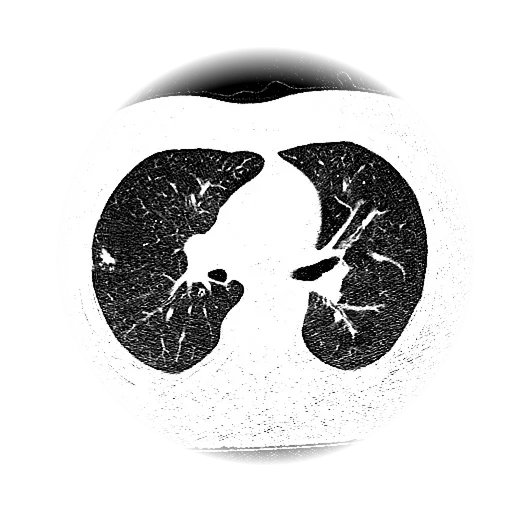

Lung Nodule Detection and Tracing Across Scans

Obvios.ai utilizes cutting-edge artificial intelligence to meticulously detect and track lung nodules, facilitating swift and precise diagnostics, thereby ensuring superior care and timely intervention for patients.